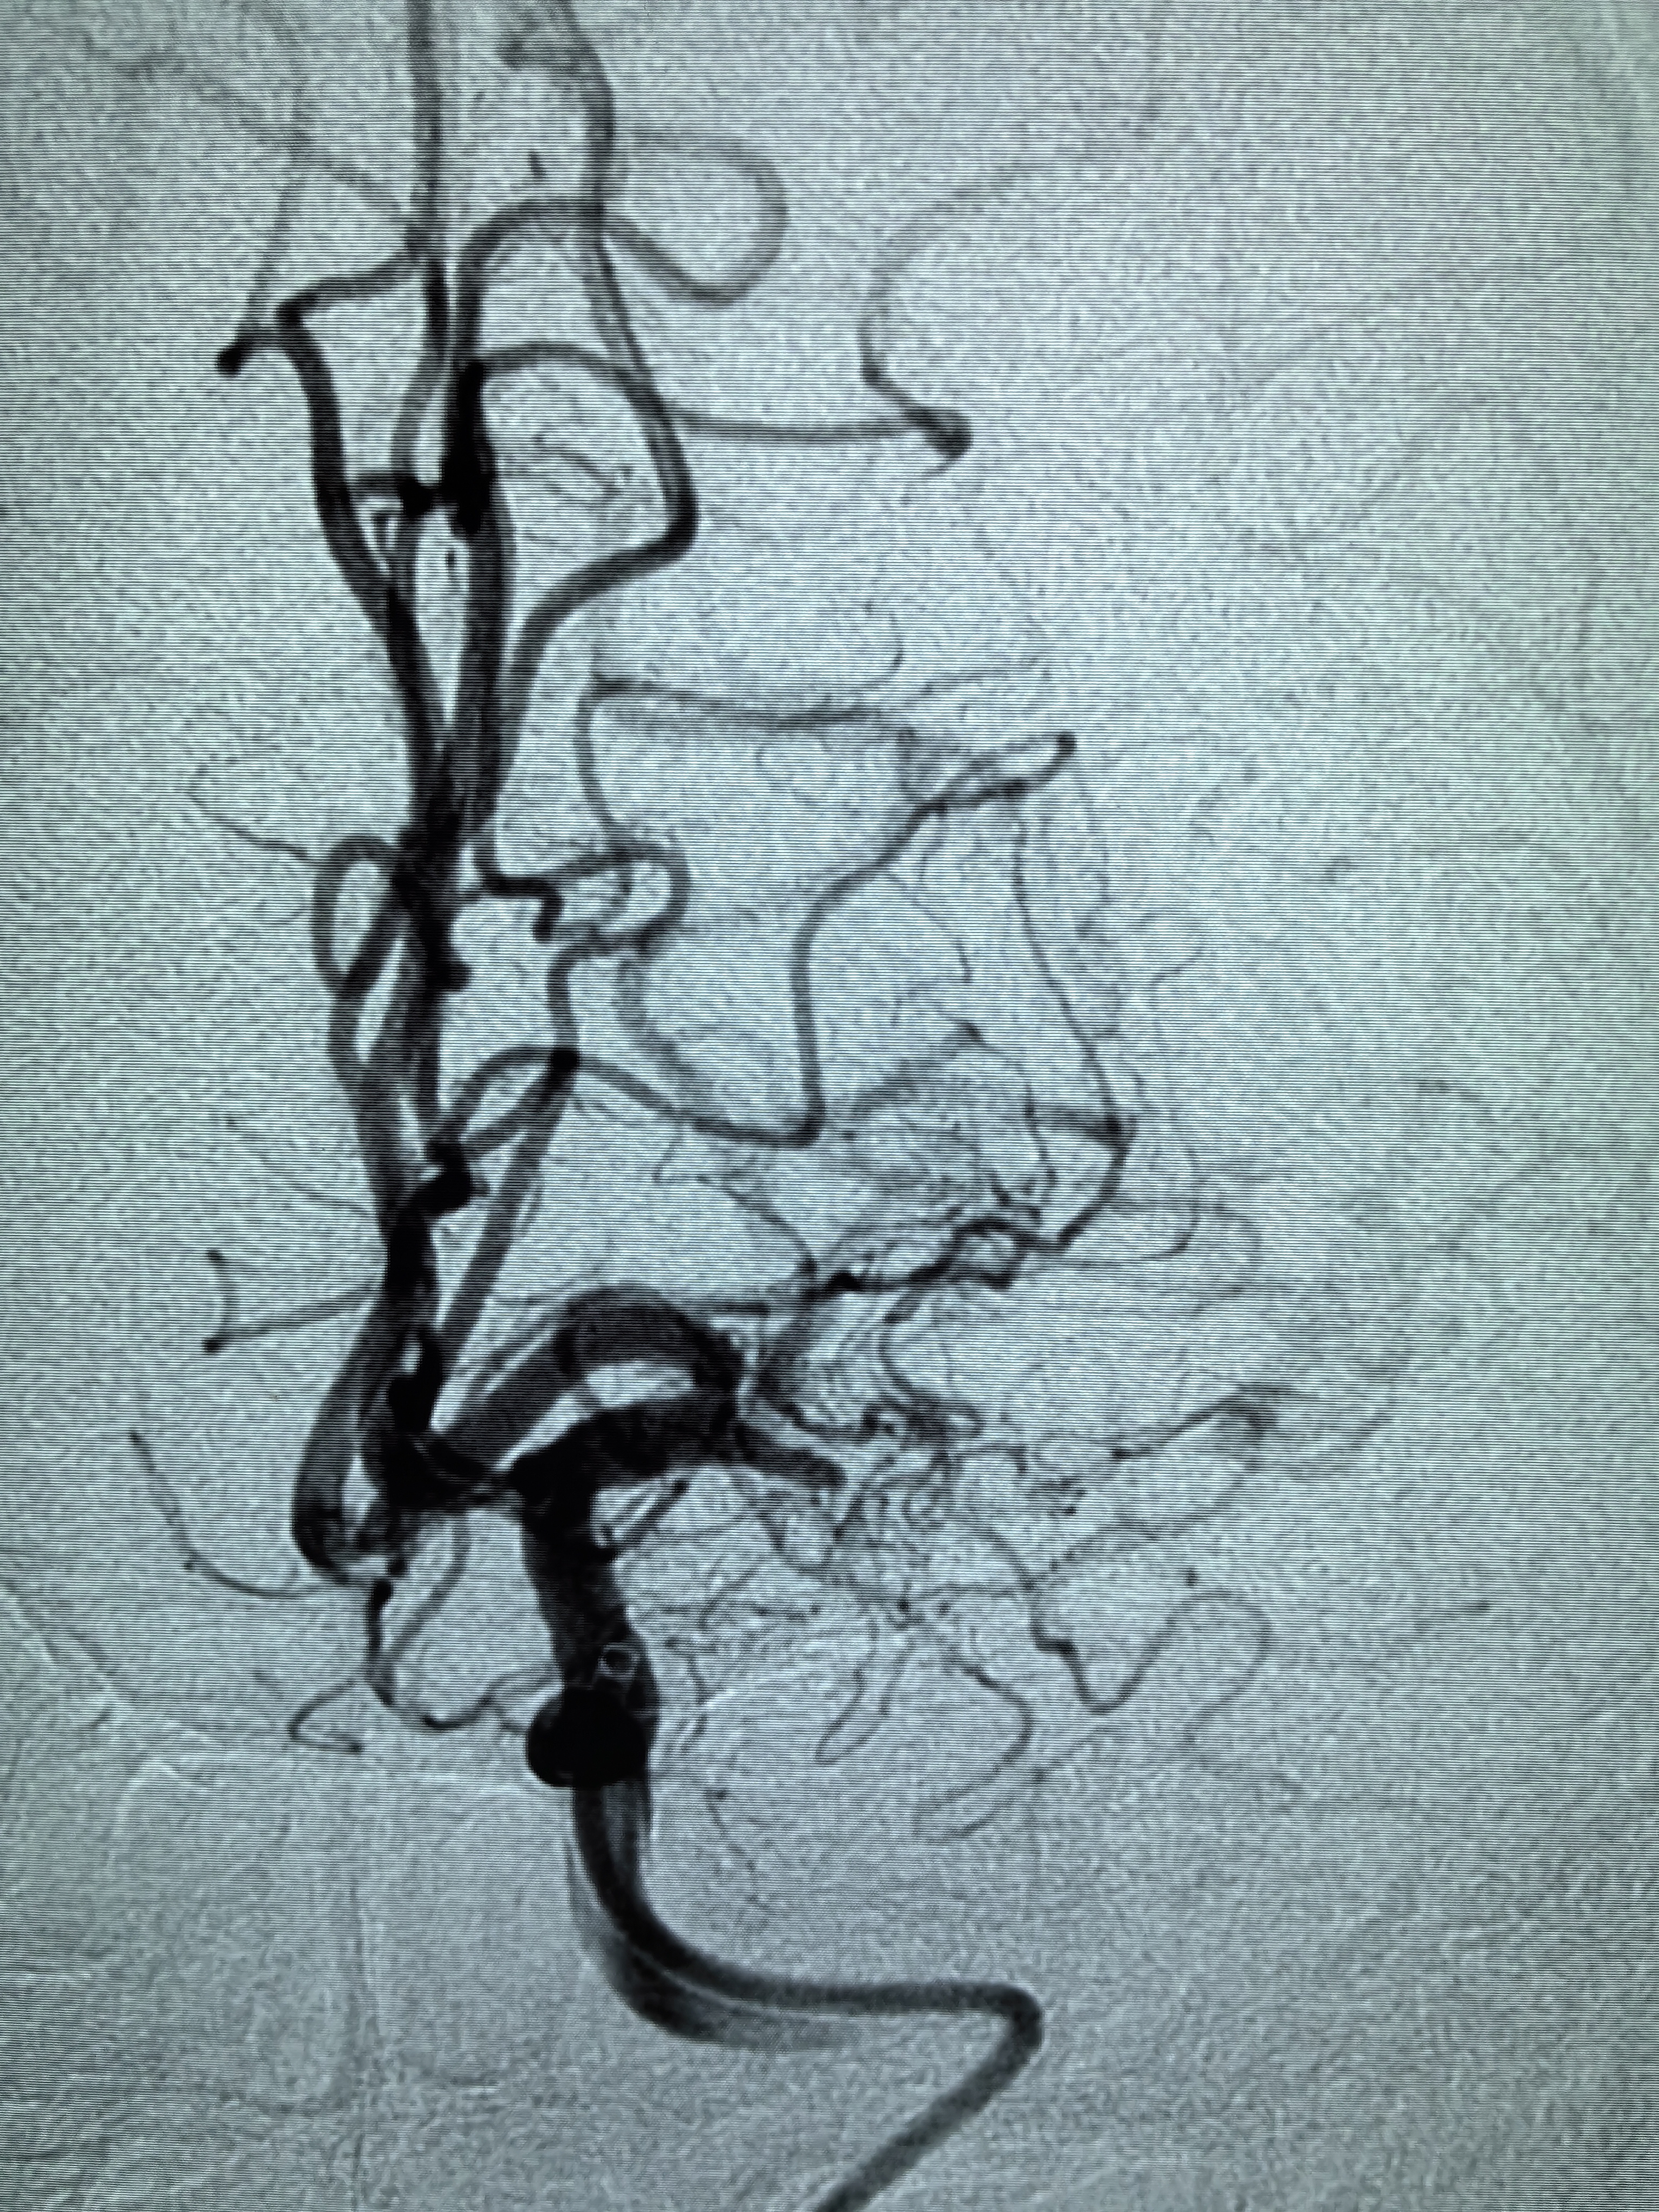

1、本例患者老年女性,系骨科术后次日醒后卒中,经核磁评估提示左侧大脑中动脉闭塞,系责任血管,患者心电图示房颤,考虑心源性栓塞可能性大。

2、本例患者SWIM技术取栓一次后血管再通,颅内血流通畅。